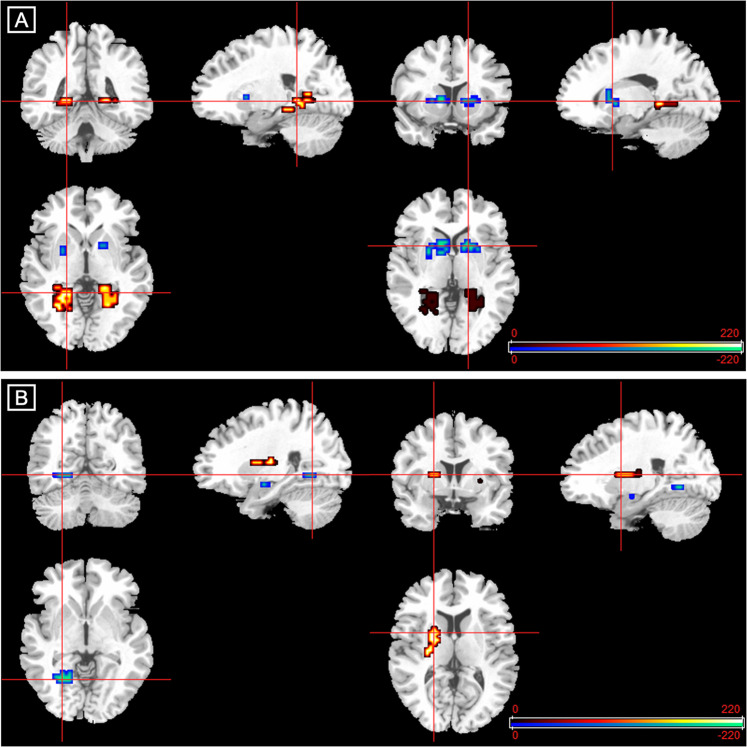

During the processing of fearful relative to neutral faces, compared to healthy controls, CHR subjects receiving placebo showed augmented activation in the left lingual gyrus and bilateral parahippocampal gyri and attenuated activation in the striatum bilaterally, including the left caudate head and putamen, the right putamen and a smaller cluster in the right caudate head (Table 2 and Fig. 1).

During fear processing, compared to CHR participants receiving placebo, those in the CBD group showed lower activation in the left parahippocampal gyrus and in a small cluster in the left amygdala and greater activation in the left putamen and in the right putamen extending to the caudate head (Table 2 and Fig. 1).